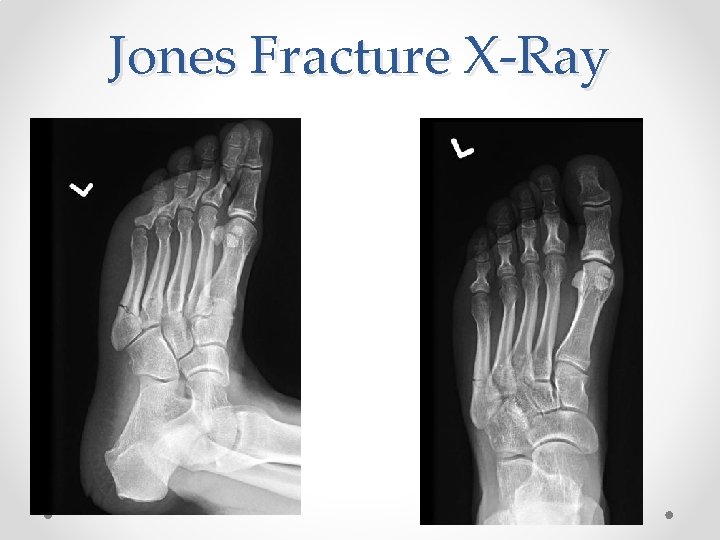

th 5 Metatarsal Fractures • Jones Fracture: • The Don’t Miss Fracture o See in sprinters, jumpers o Watershed Region/Poor blood flow = Poor healing, risk of nonunion o Treatment: • Referral to Orthopedics or Podiatry • Splint in ER and make Non-weight bearing • Non-weight bearing with cast for 4 -6 weeks followed by 4 -6 weeks in walking boot • ~ 75% heal with non-operative treatment • If athlete, often orthopedic pinning required • 30 -50% will re-fracture

Jones Fracture X-Ray